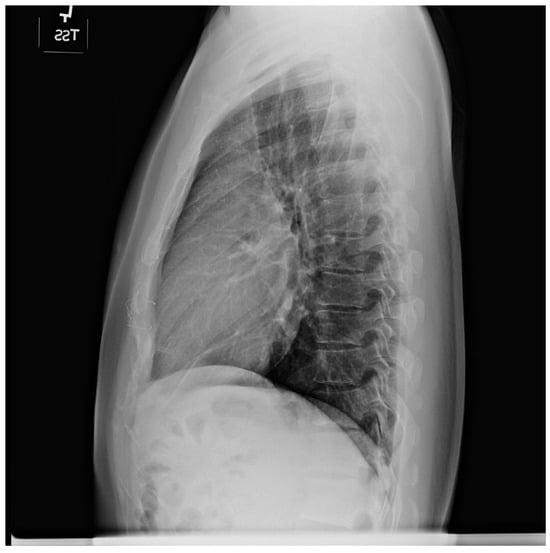

Figure 9.

Posteroanterior chest X-ray of sinus venosus atrial septal defect. This chest X-ray is of a 24-year-old female with a sinus venosus atrial septal defect and anomalous right upper pulmonary venous drainage to the superior vena cava. The image is well centered and there is a good inspiration. The cardiothoracic ratio is increased, the pulmonary artery segment is increased and the pulmonary vascularity is plethoric. Also note that there is a right-sided aortic arch (blue dots). This allows the enlarged pulmonary trunk to be better visualized because the thoracic aorta does not obscure it. Because she had dyspnea, fatigue and exercise intolerance she underwent surgical repair of the ASD and redirection of the right upper pulmonary vein to the left atrium. Her postoperative CXR showed decrease in C-T ratio and pulmonary vascularity. Her symptoms resolved.